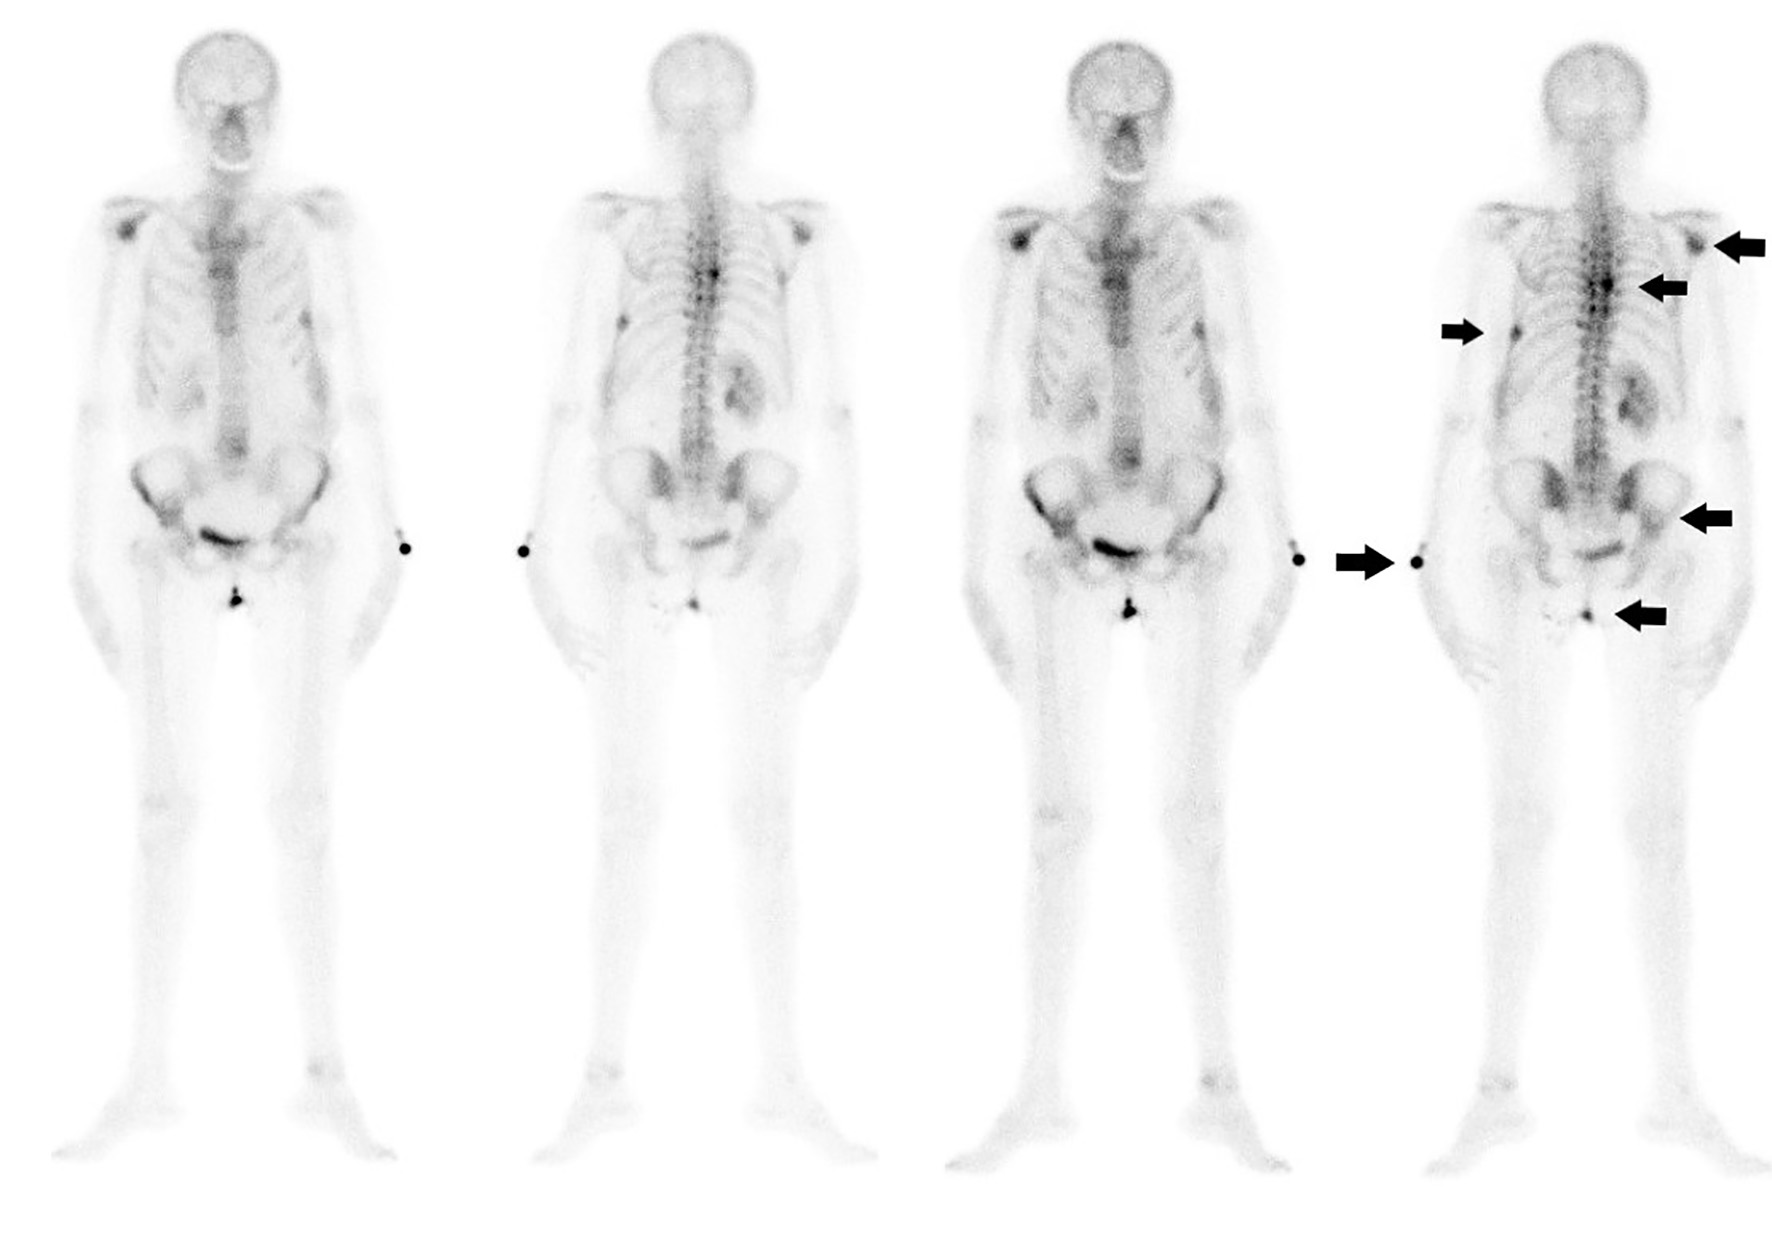

A 63-year-old female patient came to our attention for lower back pain. Her past medical history was significant for hypertension and pulmonary sarcoidosis treated with steroids. Neurological examination revealed a lumbar spinal syndrome without motor deficit. After failure of medical management, spinal computed tomography (CT) scan was performed, demonstrating a spinal lesion of 24 × 23 mm at the seventh thoracic vertebra (Fig. 1). A thoraco-abdomen CT scan revealed an 86 × 61 × 79 mm mass at the left kidney (Fig. 2) with multiple right pulmonary nodules and six bone lesions confirmed at the bone scan (Fig. 3). At diagnosis, Karnofsky Performance Status (KPS) was 80. The International Metastatic RCC Database Consortium (IMDC) risk score was intermediate and the Memorial Sloan-Kettering Cancer Center (MSKCC) score was intermediate. After multidisciplinary discussion, the patient underwent open trans-peritoneal left radical nephrectomy. The histology results described a ccRCC grade 2 with tumor extension in segmental (muscle-containing) venal branches and perirenal fat with clear margins (pathological T3aR0Nx). One month after surgery, she developed signs of spinal cord compression with neurological deficits and underwent emergency spinal decompression with a D7 laminectomy and stabilization of D5/D9. After neurosurgical operation and physiotherapy, she achieved complete remission of back pain and neurological deficits. A radiotherapy treatment of the vertebral metastases after surgery was avoided in order not to jeopardize complete functional recovery. The follow-up thoraco-abdomen CT scan after 3 months ruled out disease progression. She is currently on an immunotherapy regimen with avelumab (anti-programmed cell death-1 ligand, programmed death ligand 1) and axitinib (a vascular endothelial growth factor receptor TKI).

![]() Click for large image | Figure 3. The 99mTc bone scan confirmed six bone metastases (arrows). |